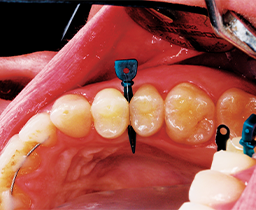

Tooth restored: a paladent ring system was used, and it was bonded with an Adhese® Universal VivaPen® (Ivoclar Vivadent). SDR flow+ (Dentsply Sirona) was used to fill the bottom 1-2 mm of box. TPH Spectra composite (Dentsply Sirona) was used to complete the restoration.

The final result was an esthetically-pleasing restored tooth (Figs. 6-7)

Fig. 6 Fig. 7